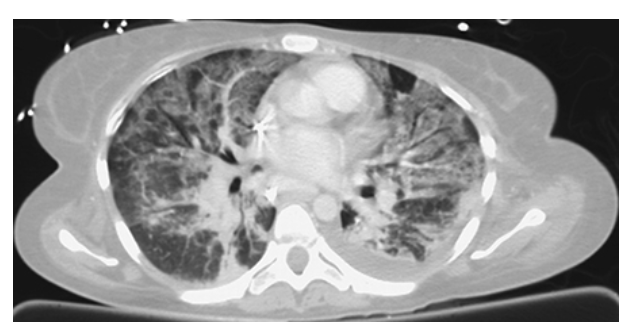

Lung window NECTs of the chest show bilateral calcified pleural plaques and pleural thickening.